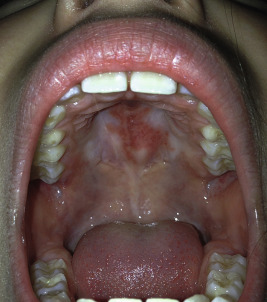

CCLE is an umbrella term used to describe lesions of discoid lupus erythematosus (DLE), lupus panniculitis, and chilblain lupus. Individual lesions of DLE are well-circumscribed, elevated, indurated red to purplish plaques with adherent scale ( Figs. 22-6 and 22-7 ) and fine telangiectasia. When untreated or as a sequela, discoid lesions may develop persistent areas of hyperpigmentation or hypopigmentation with atrophy. Discoid lesions can be asymmetric and are often exacerbated by exposure to UV light. DLE is most commonly found on the face, often with lesions on the ear helices and conchal bowls. Although the face is often the sole site of DLE without SLE, the scalp, arms, legs, hands, fingers, back, chest, abdomen, and even mucosal areas ( Fig. 22-8 ) may also be involved. At times the openings of hair follicles are dilated and plugged by an overlying scale. If the scale is thick enough, it can be lifted off in one piece. The undersurface then reveals follicular projections that resemble carpet tacks, a characteristic sign of LE. Discoid lesions have been described in a linear orientation that follows the lines of Blaschko.

Mucosal membrane lesions (gingivitis, mucosal hemorrhage, erosions, and small ulcerations) are seen in 3% of patients with CLE and in up to 30% of pediatric patients with the systemic form of the disorder. A silvery whitening of the vermilion border of the lips is highly characteristic, and the lips may show slight thickening, roughness, and redness, with or without superficial ulceration and crusting ( Fig. 22-14 ). The gingival, buccal, and nasal mucosae may also appear red, edematous, friable, and eroded, or may exhibit silvery white changes.